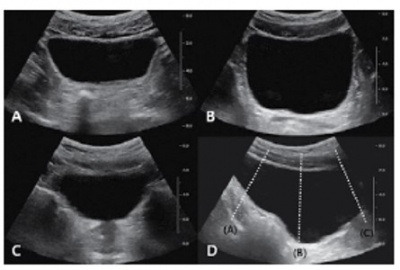

소변으로 방광이 충분히 충만한 상태에서 검사를 시행한다. 대한초음파의학회에서 권장하는 방광 초음파 검사의 표준 영상 항목은 다음과 같다. 첫째, 방광의 위쪽과 중간 부위 그리고 방광의 경부의 횡단면 영상(transverse image)을 얻는다. 둘째, 방광 중간 부위의 시상면 영상(longitudinal image)을 얻는다(Fig. 11). 방광염(cystitis)의 초음파 소견은 흔히 정상 소견이지만, 심한 경우에 방광벽이 두꺼워지고 불규칙한 점막 주름이 관찰될 수 있다. 신경인성 방광(neurogenic bladder)에서는 방광벽의 육주(trabeculation)와 방광게실(diverticulum)이 관찰되며, 방광 내압의 증가 및 방광요관 역류(vesicoureteral reflux)로 인해 수신증과 요관의 확장이 동반될 수 있다. 방광의 악성종양 대부분은 요로상피암이며 방광 내강으로 돌출된 종괴의 형태가 가장 흔하다(Fig. 12). 또한, 동시기 암(synchronous cancer)이 방광의 다른 부위, 요관 및 신우 등에서 동반될 수 있으므로 방광암이 의심될 때에는 전반적인 요로계의 관찰이 필요하다.

신장 및 방광 11.jpg

Fig. 11. 방광 초음파 검사의 표준 영상 항목. (A-C) 각각 방광 위쪽과 중간 부위, 그리고 방광 경부의 횡단면 영상. (D) 방광 중간 부위의 시상면 영상. 점선은 각각의 횡단면 영상을 얻은 부위